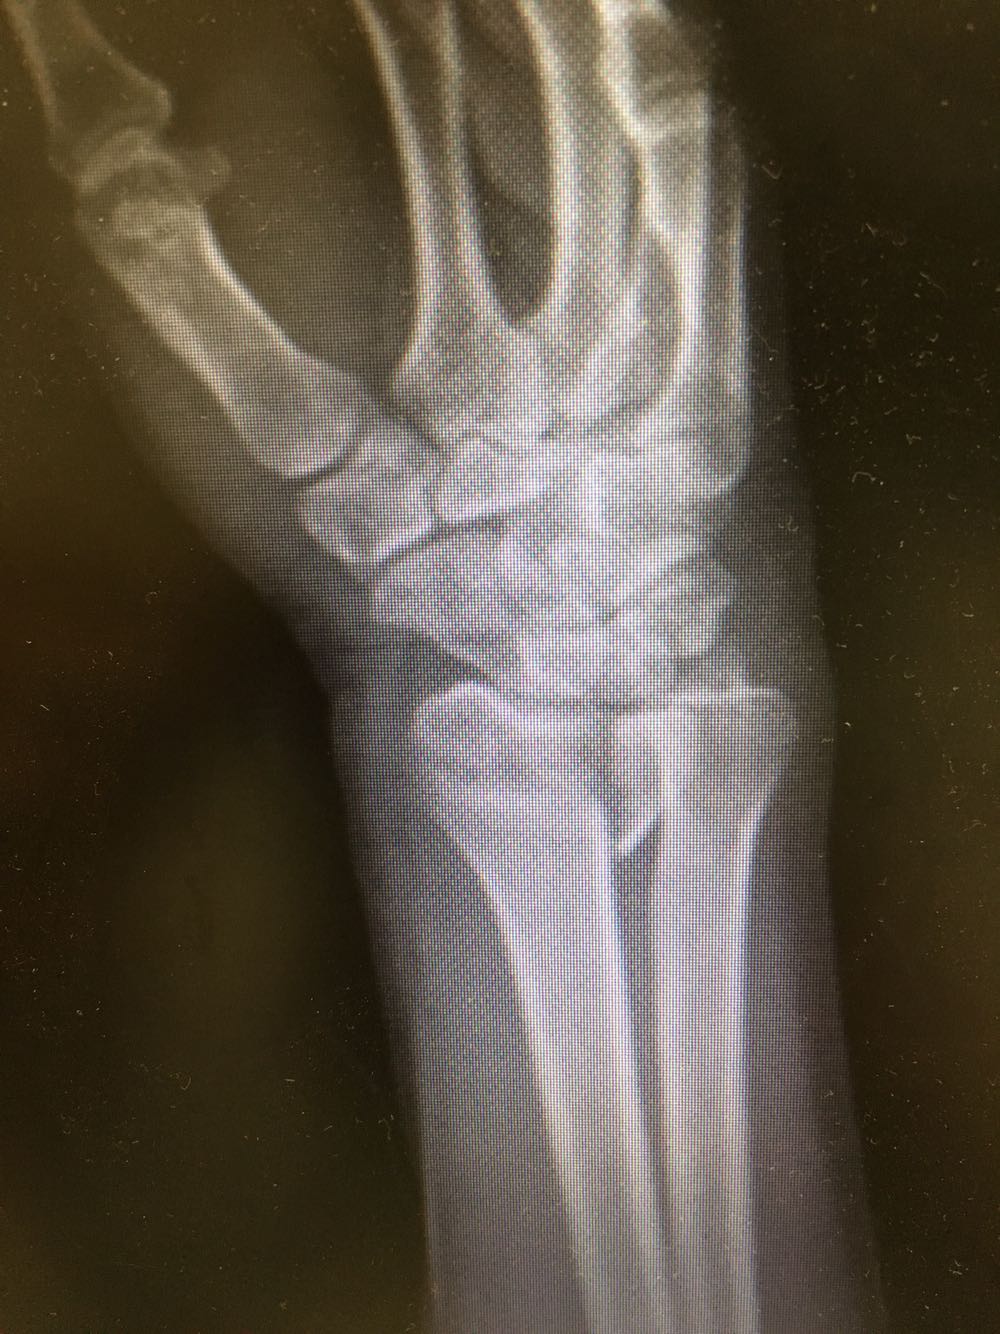

尺桡骨远端骨折一例

尺骨桡骨远端骨折

患者,女性,62岁 主诉:外伤致右腕部疼痛伴活动受限8小时 现病史:患者于8小时前受外伤后出现右侧腕部剧烈疼痛,后出现肿胀伴活动障碍,否认头晕头痛、恶心呕吐等不适,遂至我院就诊,查X片示:右侧尺桡骨远端骨折,现为进一步诊治收治入院,发病以来,神清,精神可,胃纳夜眠可,二便无殊,体重无明显变化。

查体:右侧腕部肿胀,压痛阳性,伴活动受限,远端肢体感觉及运动正常。 辅检:见现病史

诊断:右侧尺桡骨远端骨折 治疗:完善术前检查后行手术内固定